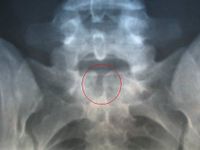

Spina bifida occulta

X-ray image of Spina bifida occulta in S-1

Occulta is Latin for "hidden". This is one of the mildest forms of spina bifida.[1]